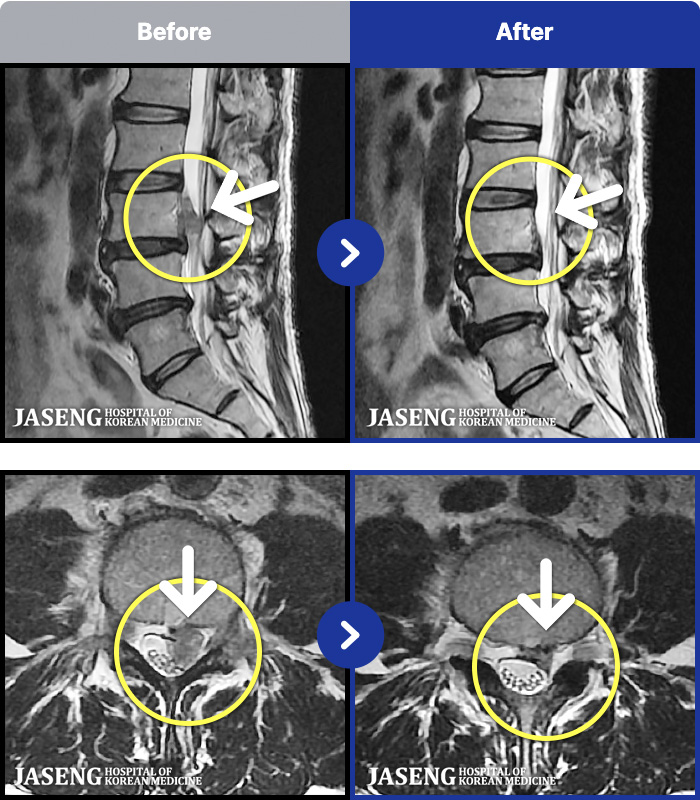

[Կñ:24.06.22~24.11.19]

[õ_㸮ũ] ö ݺ ؽ Ͽ

No.100

ȸ 599

2024.11.29